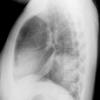

Case 2 Lingular pneum PA

Date: 04/17/2005

Views: 5958